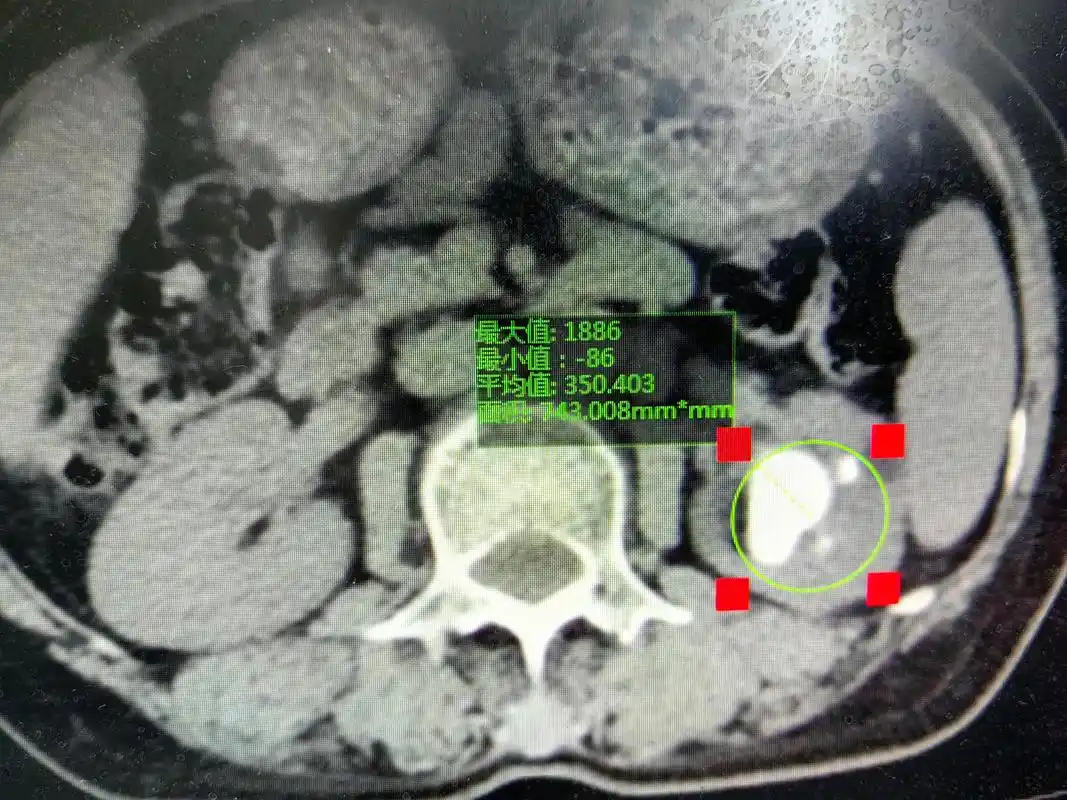

肾结石的硬度已经颠覆了医生的认知,肾结石的ct值了解一下

男性患者,体检发现双肾结石1年,左肾铸型结石:6.0×5.9 - 抖音

肾结石输尿管结石的ct及kub阅片

最新进展 > 正文 后进行ct平扫时,除了发现左侧肾盂结石以外,细心的